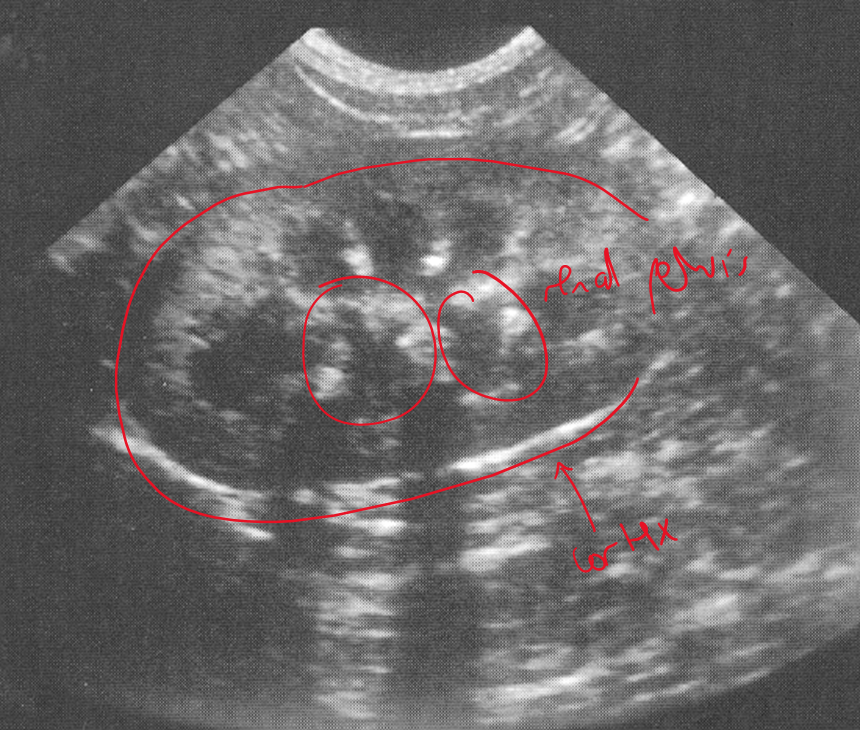

What is being shown here?

R = Dilated renal pelvis

Bottom = dilalted proximal ureter

L = ureters dilated by couple mms —> obstruction of urinary outflow